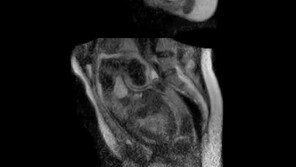

![[영상] 출산 순간 MRI 영상 최초 공개](https://dimg.donga.com/a/296/167/95/2/wps/NEWS/IMAGE/2012/06/29/47391735.1.jpg)

▲동영상=출산 순간 MRI 영상 최초 공개 산모가 아기를 출산하는 과정의 순간을 MRI로 촬영한 영상이 최초로 제작 공개되어 뜨거운 관심을 모으고 있다.영국 데일리메일 27일자 보도에 따르면, 독일 베를린의 차리테 대학병원은 특별 제작한 ‘오픈 MRI 스캐너’를 이용해 태아가 산모의 …